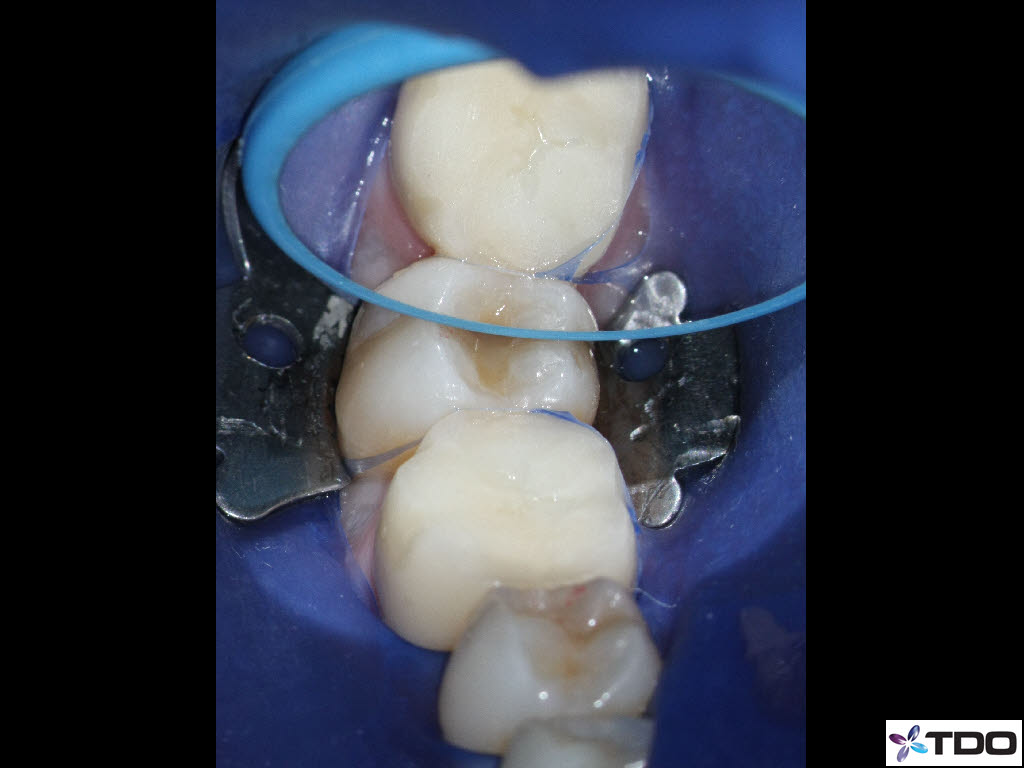

In the hierarchy of dentin conservation the existing restorative has the lowest priority and it quite frankly gets in the way of our access to the root canal system. But, after practicing directed dentin conservation for a while, you sometimes get lucky. The patient is 40yo. She was symptomatic at the time of treatment and interestingly the mesiobuccal canal was partially vital while the mesiolingual, distobuccal and distolingual canals were partially necrotic. She was asymptomatic at the completion visit as well as at the follow-up appointments.

Hi Gergely. The crown was less than two weeks old when the patient was first seen in my office. The previous crown was 15 yrs old and was seldom sensitive; the RD replaced the crown due to an “open margin.” Heat/cold sensitivity ensued after the crown prep. Four days after the permanent crown was cemented the patient woke up with severe throbbing pain and the temp sensitivity became worse. When she presented to my office she reported severe biting tenderness and tender submandibular lymph nodes.